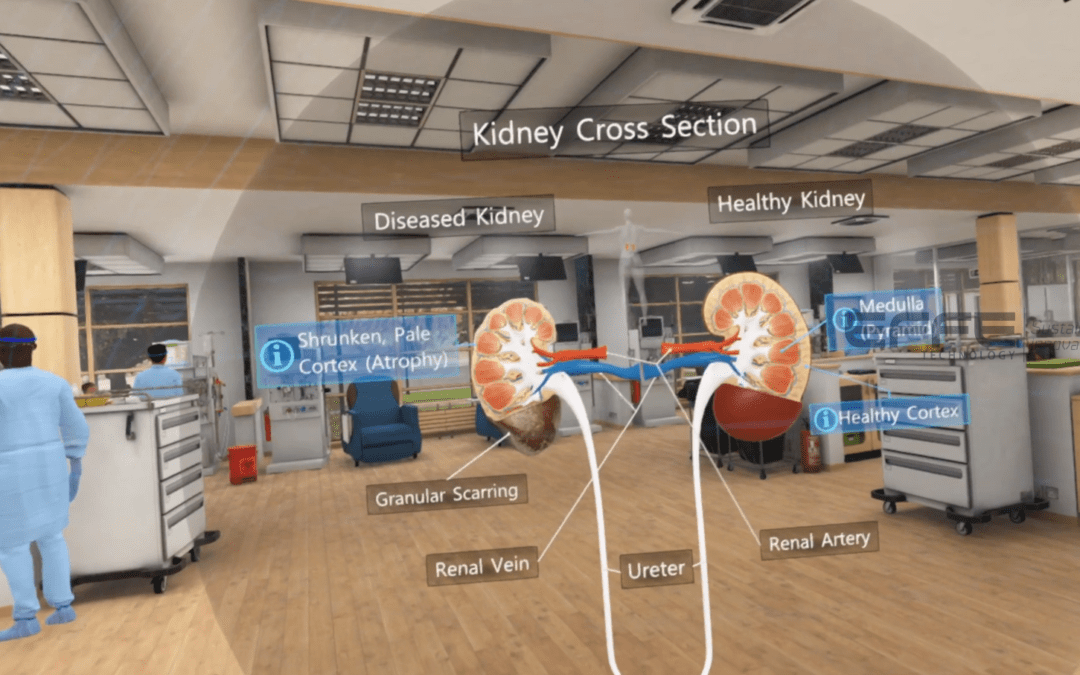

Overview A precise understanding of renal structure is essential for accurate diagnosis, dialysis planning, and...

Overview Understanding kidney anatomy and renal physiology is critical for accurate diagnosis, dialysis management,...